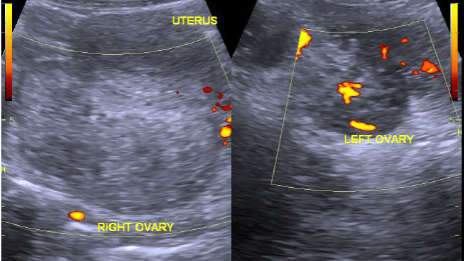

Ovarian Torsion

November 3, 2020

Take the Quiz